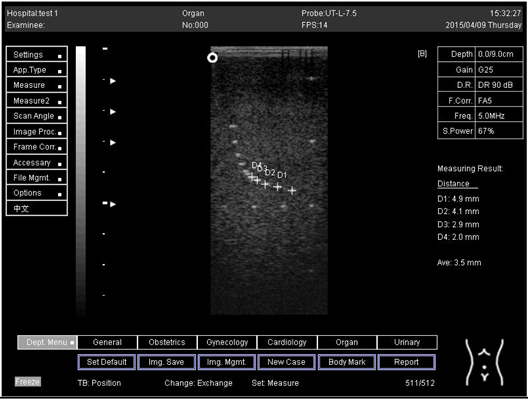

9.0 Axial resolution

Biomimetics 07 00130 i001

D1 = 4.9

D2 = 4.1

D3 = 3.1

D4 = 2.2

Lateral resolution

Biomimetics 07 00130 i002

D1 = 5.0

D2 = 4.0

D3 = 3.0